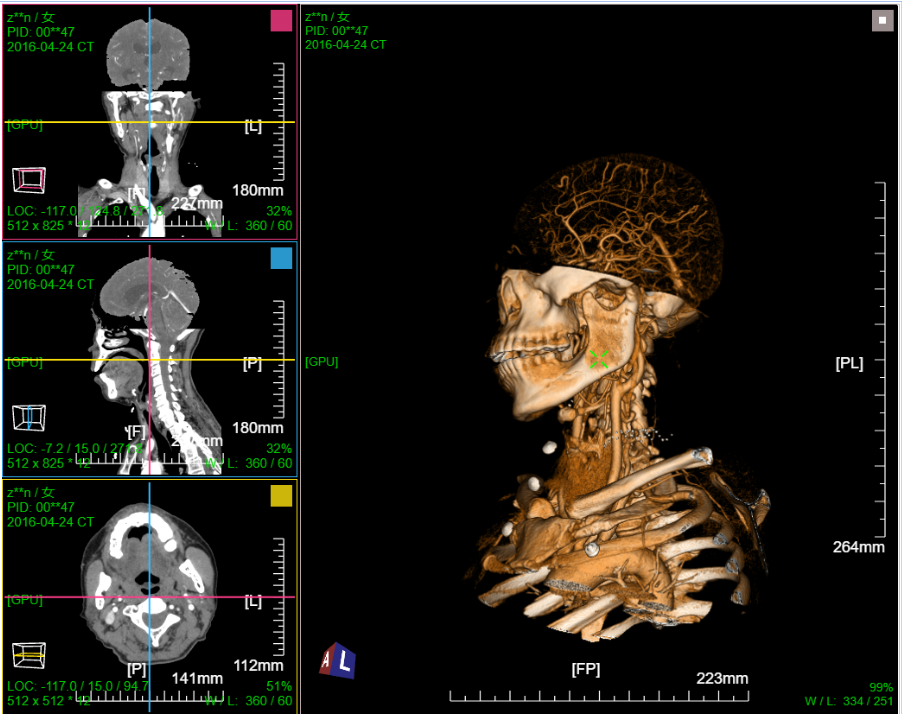

八、三维浏览功能操作和截图

左键双击MPR窗口可在MPR三窗口和1x1窗口间切换;三维渲染窗口左键双击在在1x1视图模式和当前视图模式切换

点击MPR窗口右上角颜色块可AXIS轴位、CORO冠位、SAGI矢位切片切换

CPR曲面重建 、厚切曲面;

VR容积渲染;鼠标右键默认实时调整当前VR传输函数

MIP 最大密度投影渲染: 鼠标右键默认实时调窗

VR渲染一键去床体:为提高去床速度,可先进行体包围盒裁剪选择含有床体的部分然后点击一键去床功能

VR渲染一键去头骨:首先进行体包围盒裁剪选择头颅部分限制区域生长范围,然后点击一键去头骨功能

三维:MPR多平面重建(支持任意旋转)、CPR任意曲线切面重建、MIP最大密度、VR容积重建、VE虚拟内窥;任意三维裁剪、一键去床、一键去头骨、快速旋转、厚切MPR(最大密度/最小密度/均值/VR); 手工/半自动分割,分割目标三维渲染; 肋骨CPR拉伸渲染、牙神经管渲染、血管CPR拉直渲染等